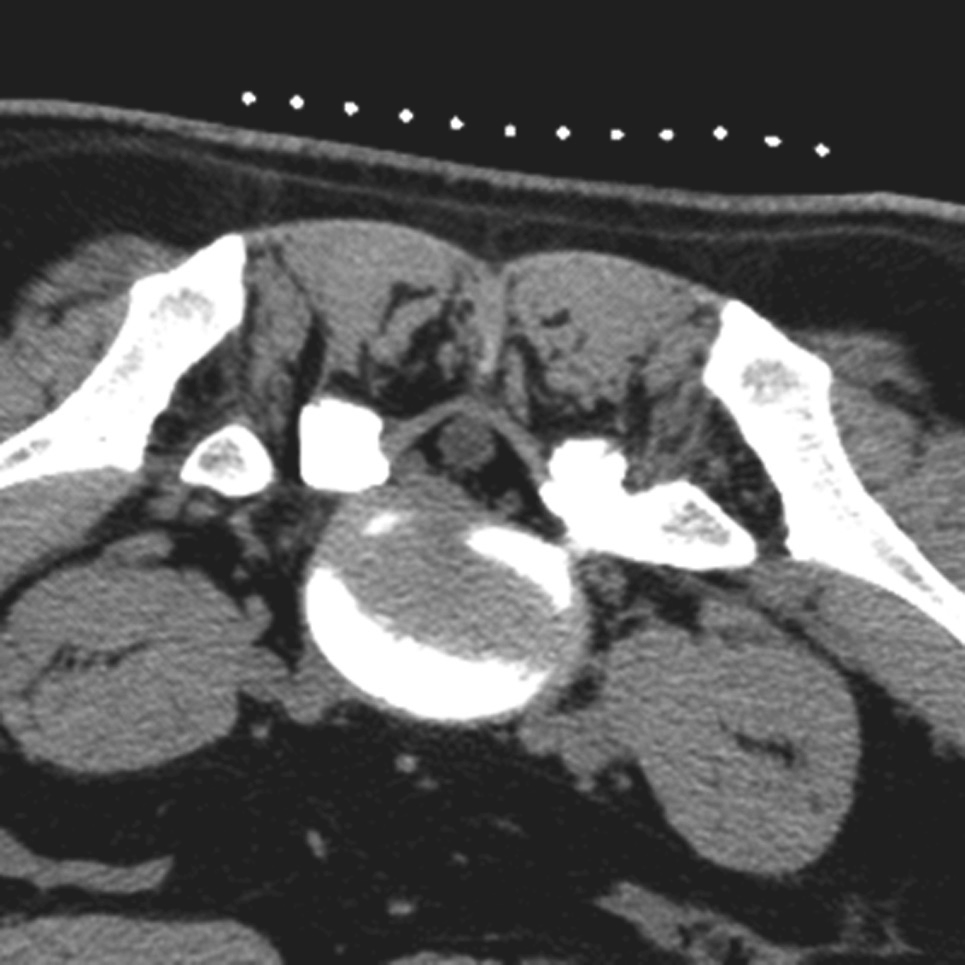

在扫描产生的多层横断面中选择出最符合穿刺要求的一层,作为设计入路和引导穿刺定位的操作平面,我们将该层称为“靶点操作平面”。根据不同的手术目的选择该平面的要求也不同:避骨入路类手术如经椎板间入路椎间盘靶点定位类,应选择具有最大程度避开神经、血管、脏器、骨质而到达靶点的平面,如图3-3-12中显而易见图B是最合适的平面;经椎间隙侧方入路时的扫描图像中(图3-3-13),图B最合适;而经骨入路类手术如经皮椎体骨折复位外固定、椎体成形术等,应选择椎弓根宽大处的平面,如图3-3-14中图B作为操作平面最合适。CT机架角度扫描的横断位平面自然也是倾斜的,而穿刺定位入路是在该平面内的,因此存在如下关系:CT机架扫描角度=靶点操作平面角度=定位针穿刺时的头足倾斜角度(图3-3-15)。

图3-3-14 沿椎弓根轴线扫描的不同层

A.椎弓根偏头侧平面;B.椎弓根中间平面;C.椎弓根偏足侧平面